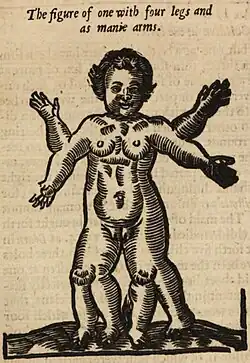

Polymelia is a birth defect in which an affected individual has more than the usual number of limbs. It is a type of dysmelia. In humans and most land-dwelling vertebrates, this means having five or more limbs. The extra limb is most commonly shrunken and/or deformed. The term is from Greek πολυ- "many", μέλεα "limbs".

- 1529: A male child was born in Germany on January 9 with all four limbs duplicated at the elbows. He was described by Ambroise Pare in Of Monsters & Prodigies.[3]